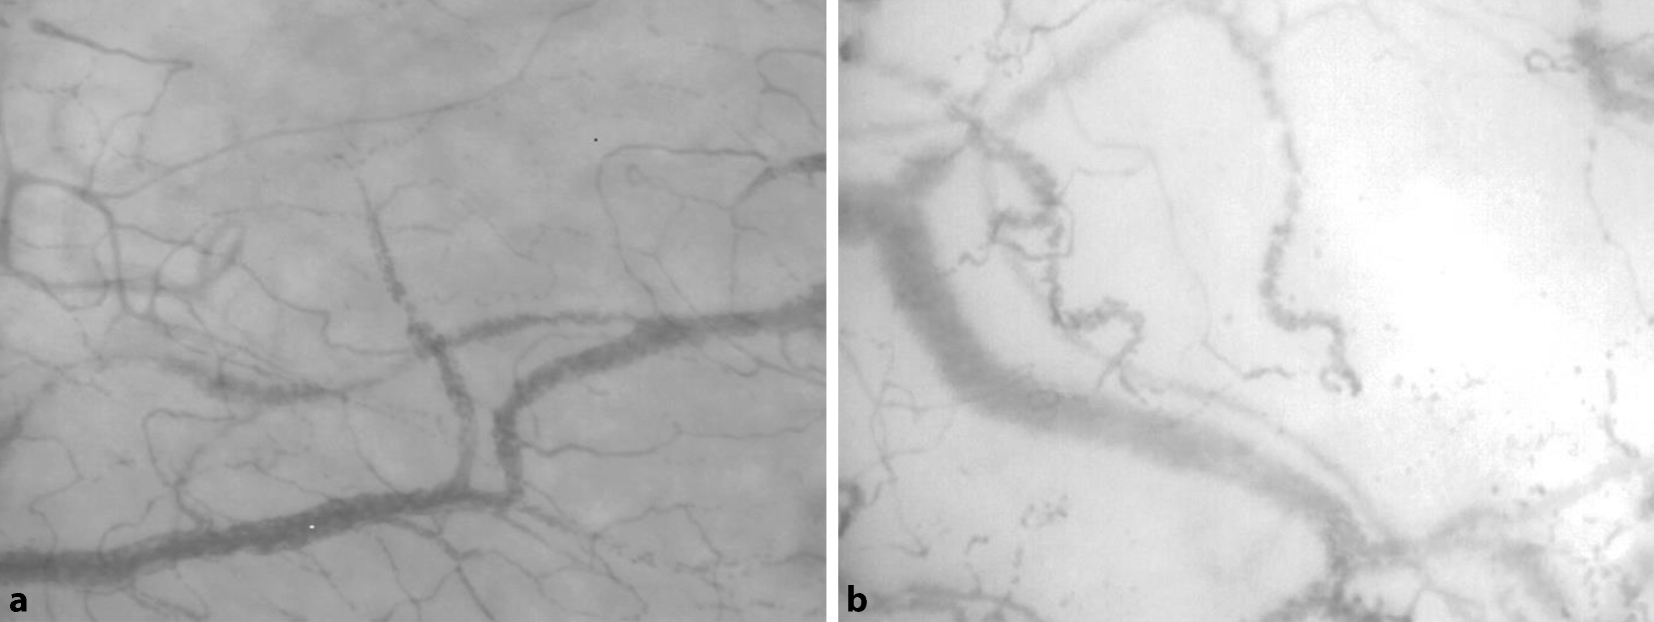

Daneben gewinnt die direkte und objektivierbare Visualisierung der Mikrozirkulation stetig an klinischer Bedeutung [9]. Diese ermöglicht Rückschlüsse auf verschiedene Eigenschaften des Endstromgebiets: Indirekte Messmethoden wie die Gewebekapnometrie (im Magen), die Laser-Doppler-Flowmetrie und die HbO2-Spektroskopie konnten sich hierbei aber nicht klinisch durchsetzen. Einen Durchbruch brachte hingegen die Entwicklung der bettseitigen Intravitalvideomikroskope „sidestream-darkfield“ (SDF, z. B. MicroScanTM; Fa. Microvision Medical, Niederlande) und Incident-Darkfield (IDF, z. B. CytoCam; Fa. Braedius Medical, Niederlande). Diese können durch Illumination und Reflexion des Gewebes das mikrovaskuläre Gefäßbett in hoher Auflösung darstellen (Abb. 1) und werden vornehmlich sublingual angewendet. Die Messung ist einfach zu erlernen und kann beliebig oft in Echtzeit wiederholt werden, während sie u. a. eine Veränderung des Lactats antizipiert [11].

Abb. 1

Repräsentative Aufnahmen der sublingualen Mikrozirkulation mittels „sidestream-darkfield“(SDF)-Intravitalmikroskopie (Fa. Microvision Medical, Niederlande). Die Mikrozirkulation wird anhand der Gefäßgröße, ihres Perfusionsstatus und ihres Flussprofils durch einen Algorithmus evaluiert. a Intakte Mikrozirkulation, b Mikrozirkulation eines kritisch kranken Patienten mit Gefäßrarifizierung